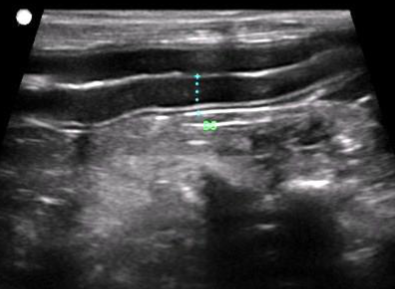

Abdominal ultrasound is a non-invasive, pain-free imaging tool that allows our veterinarians to see inside your pet’s abdomen in real time — helping us assess organs such as the liver, kidneys, spleen, bladder, and intestines with incredible detail.

*Earlier detection of internal diseases and abnormalities

*More accurate diagnoses without the need for surgery